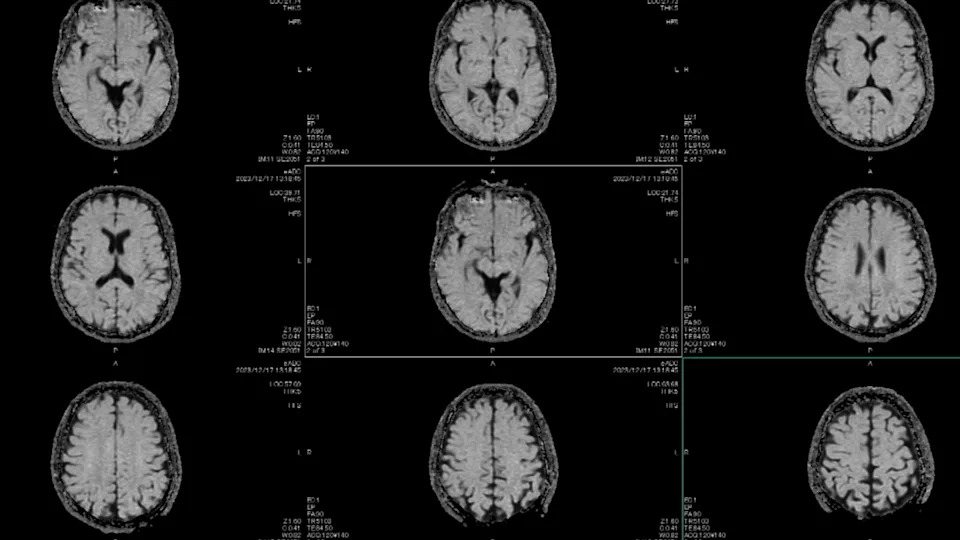

10. “Not the patient himself, but his mom. This child was 18 months old and was admitted due to constipation. We were giving him medicines for that and it was getting better but the mom started to insist we get an MRI of his brain.”

Tunvarat Pruksachat / Getty Images

“We refused at first because we did not think there was any need for it and thought it was a waste of resources. Eventually, we gave in and it turned out that he had a massive brain tumor (medulloblastoma).”